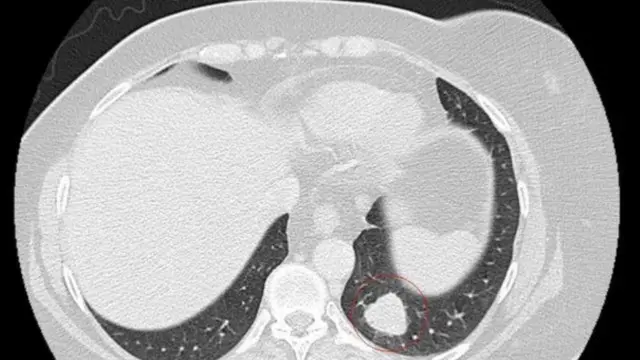

وصنف الورم الذي أصاب وجهها بأنه ورم حميد لكنه في الحقيقة كان ورما سرطانيا وانتشر إلى الرئة. وقال الأطباء إنها ستعيش فقط ما بين 18 إلى 24 شهرا.